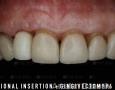

12 Months

15 Months